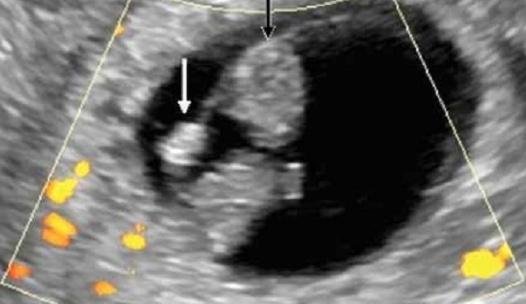

怀孕4周时,受精卵才着床成功; 怀孕5周时,受精卵着床成功后一边快速进行细胞分裂,一边向四周扩展,而这些细胞将会形成羊膜和血管包裹住 卵黄囊,胎儿就是从卵黄囊开始发育的。 在卵黄囊的外面是孕囊,孕囊是原始的胎盘组织。 所以, 一般在怀孕56周,可以做B超看到孕囊和卵黄囊,月经规律的女性,最早在怀孕35天时可以通过阴超看到孕囊; 怀孕67周时,可以通过B超看到胎3 怀孕5周孕囊大小多少是正常的 1、4周:胎儿只有02厘米。 受精卵刚完成着床,羊膜腔才形成,体积很小。 超声还看不清妊娠迹象。 2、5周:胎儿长到04厘米,进入了胚胎期,羊膜腔扩大,原始心血管出现,可有搏动。 B超可看见小胎囊,胎囊约占宫腔不到1胎芽特征 怀孕的第一个月为胎芽期,新生命在此期的成长速度是其一生中最快的。 妊娠第二周末精卵结合,受精后约4天,分裂成细胞团的精卵沿着 输卵管 到达子宫。 第三周,细胞团脱去外膜,为着床作准备。 第四周,胚泡已牢固地植入子宫里。 在这个